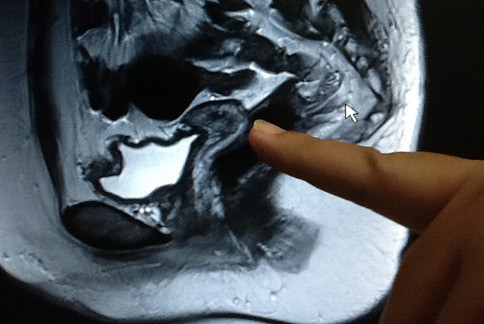

婦產科醫師蔡鋒博指出,一位女性結婚5年,現年才29歲,卻罹患不孕症5年,近日來求診,問診中,自述表達想要懷孕,並帶了一張醫學中心做的MRI核磁共振檢查光碟,資料顯示,患者子宮只有2公分長度(正常是7公分),且陰道細如羊腸。

由於沒有子宮頸,不能生小孩。蔡鋒博醫師質疑,如果沒有子宮頸,她怎麼會有月經小小點狀出血?因此,幫她做了陰道超音波,雖然卵巢功能正常,但卻發現子宮頸有一個小小的洞口,但是面對這樣一個子宮小於2公分,陰道細如羊腸的患者,初步研判,自然懷孕機率幾乎等於零。